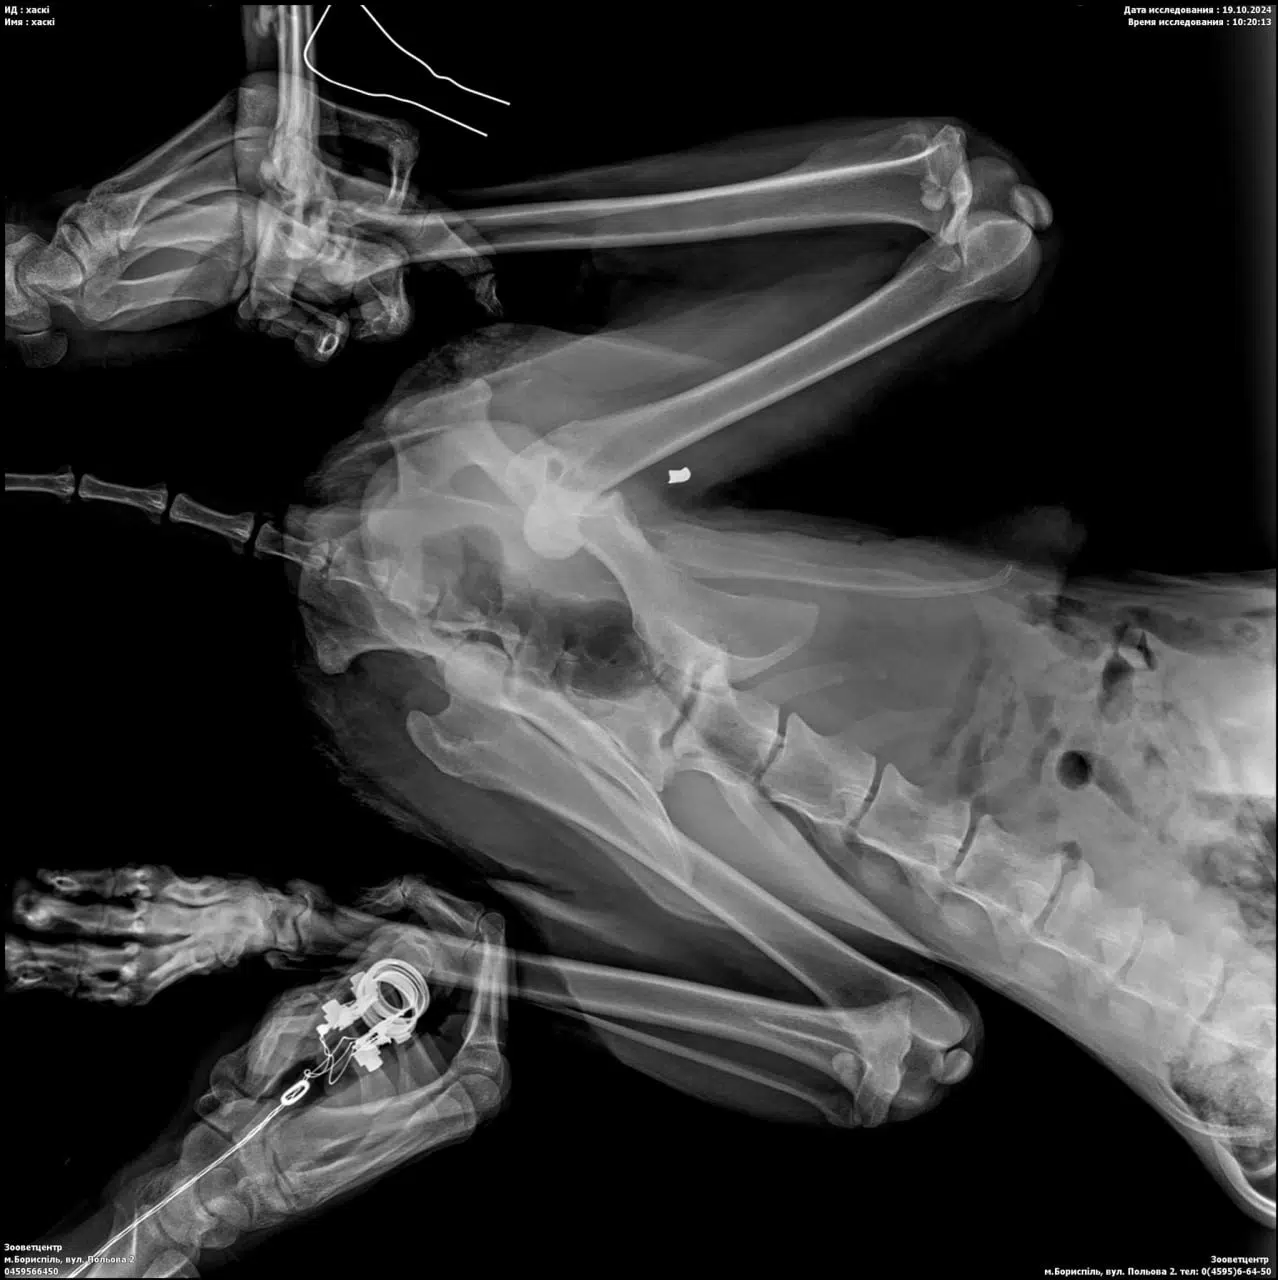

Неможливо збагнути, які страшні муки відчувала тварина. У Хенка виявили кулю в задній лапі, вивих стегна, глибокі рани по всьому тілу, які роз’їдали черви, розрив статевих органів, зламані ребра, що призвело до потрапляння повітря в легені, критичне зневоднення, сильний запальний процес, анемію, больовий шок… Столичні фахівці почали робити все можливе для спасіння хаскі.